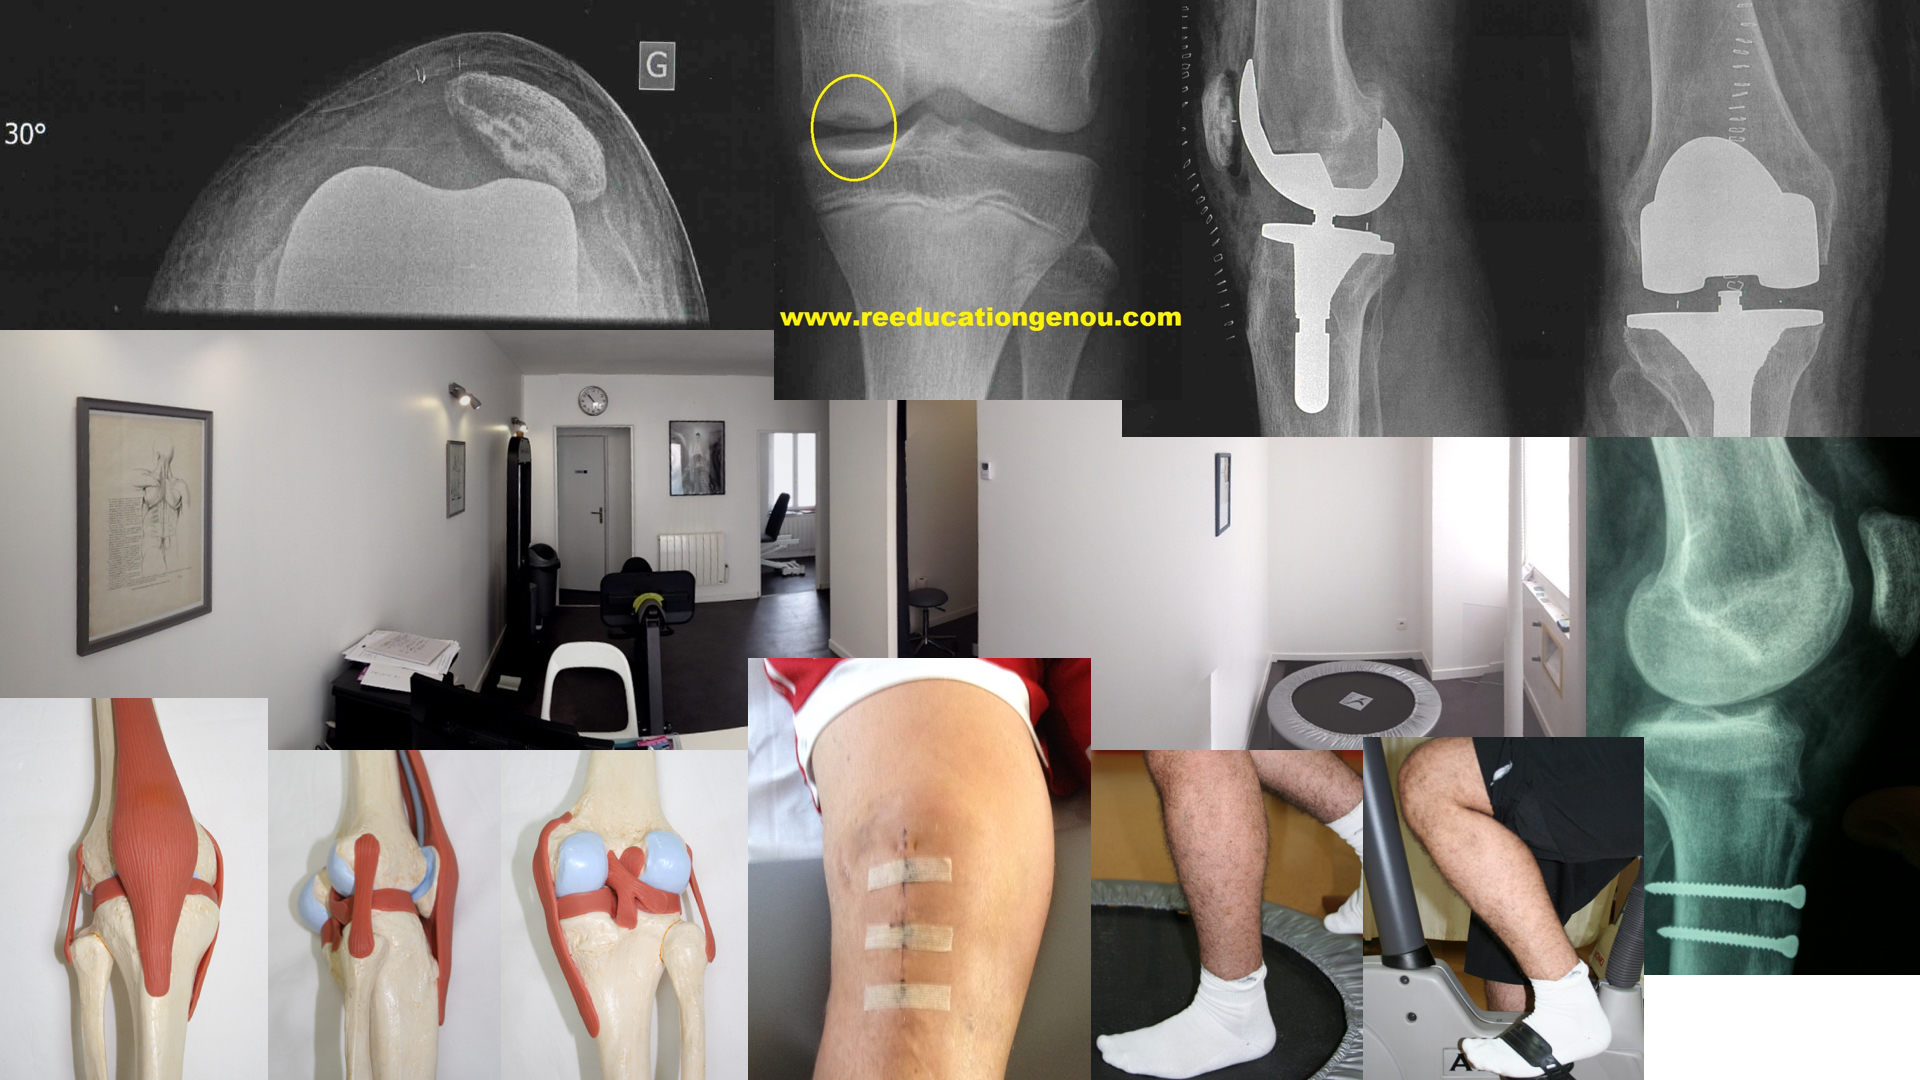

• à la jonction tendon-os : c'est une enthésopathie (l'enthèse étant le lieu d'attache du tendon sur l'os avec un angle de 30°)

Tendon rotulien et pointe de rotule

Il s'agit d'un excès de travail de l'appareil extenseur (quadriceps et son tendon sur la rotule, la rotule et son tendon sur le tibia). Cela arrive en général quand la pratique sportive dérive trop vers la propulsion / réception (jumper's knee) ou quand il existe une asymétrie de souplesse entre le quadriceps et les ischios-jambiers. Attention cependant les ruptures partielles du tendon rotulien produisent les mêmes symptomes (l'IRM est d'ailleurs souvent difficile à interpréter car cette petite ligne noire/sombres passe souvent inaperçue)